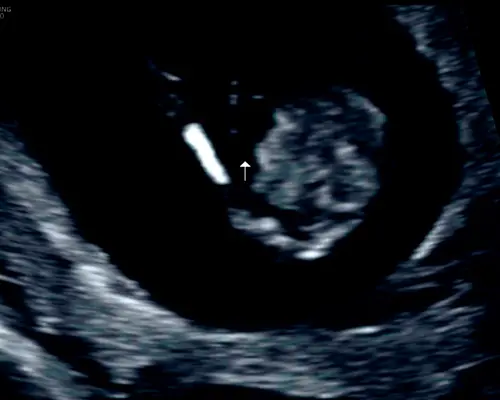

Dit is een echo vanaf de onderkant bij mijn zoon, toen 13 weken echo. Duidelijk twee benen. Mijn zoon was echt heeeeeeel duidelijk een jongen een week of twee na deze echo maar hier dus eigenlijk zo goed als niet zichtbaar

Het is (zover ik zie) in elk geval geen echobeeld van de onderkant, dan zou je 2 benen zien zoals op het beeld wat eerder al gereageerd is in een foto.